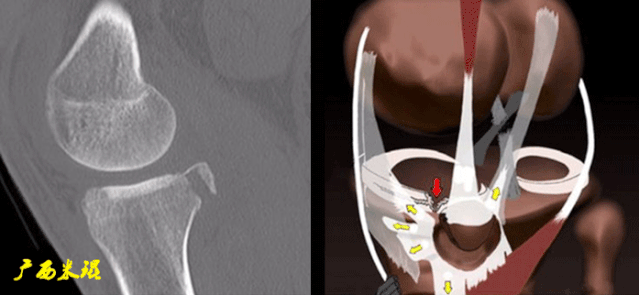

CT

-

5)Segond骨折:

胫骨平台前外侧撕脱骨折(胫骨平台腓骨尖上方,关节线下方的撕脱骨折),多因为下肢过度内翻加内旋暴力所致。

骨折本身无特殊治疗,但其强烈提示ACL损伤(75–100%)。